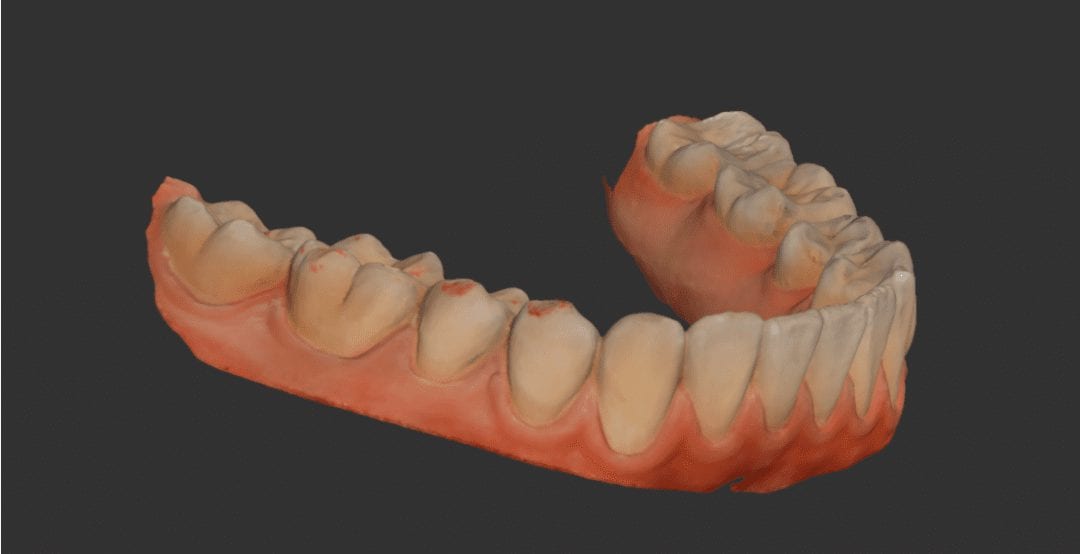

This is a case that demonstrates how a full arch scan is taken with the Medit i500. We generally recommend that you establish a good “purchase point” where you can […]